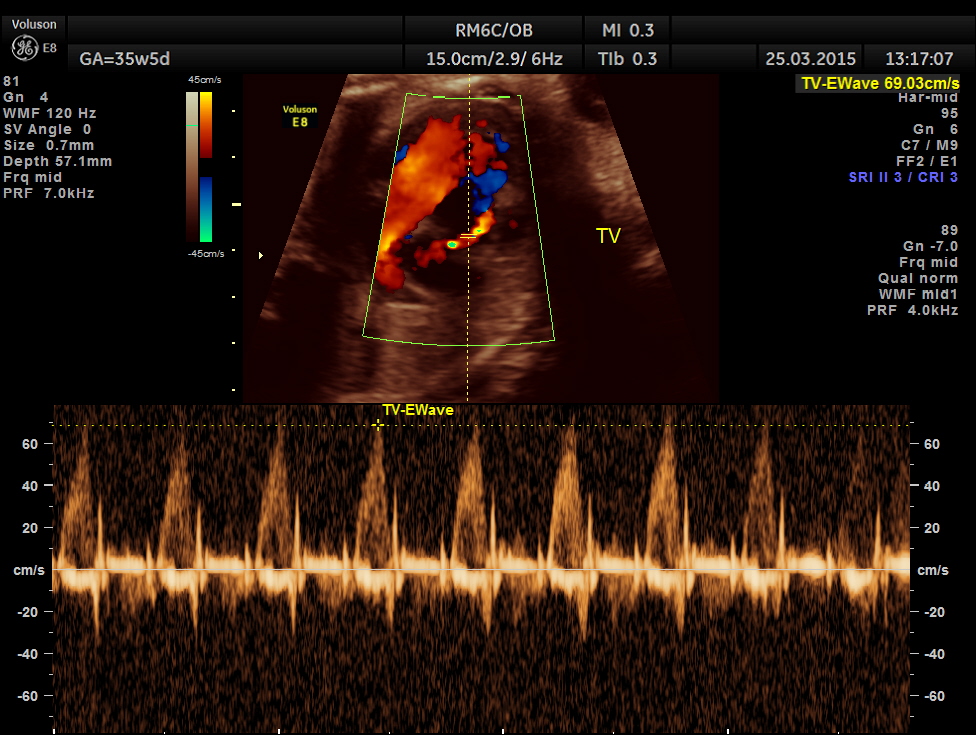

Tricuspid doppler flow.